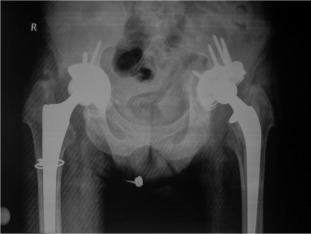

Six years after right side, five years after left side THA.

Fig. 4.

There were 61 patients (50 male, 11 female) with 105 affected hips (72% bilateral, 28% unilateral). The average patient age at surgery was 41.3 ± 10.2 years old. The age of patients at THA was as follows: <30 years for 14 patients (23 hips), 31–50 years for 41 patients (73 hips) and >50 years for 6 patients (9 hips) (Graph 1 ). The younger age at diagnosis (<30 years old) of AS was correlated with younger age at THA (p < 0.05). Bone ankylosis was detected in 37 (35%) and acetabular protrusion was noticed in 18 (17%) hips in pre-operative radiographs (Fig. 1 , Fig. 2 , Fig. 3  ;  Fig. 4 ) (Table 1 ). The mean pre-operative flexion contracture was 20.3°±21.8°. In patients without ankylosis, the mean total hip range of motion (ROM) was 67.8°±25.7°.